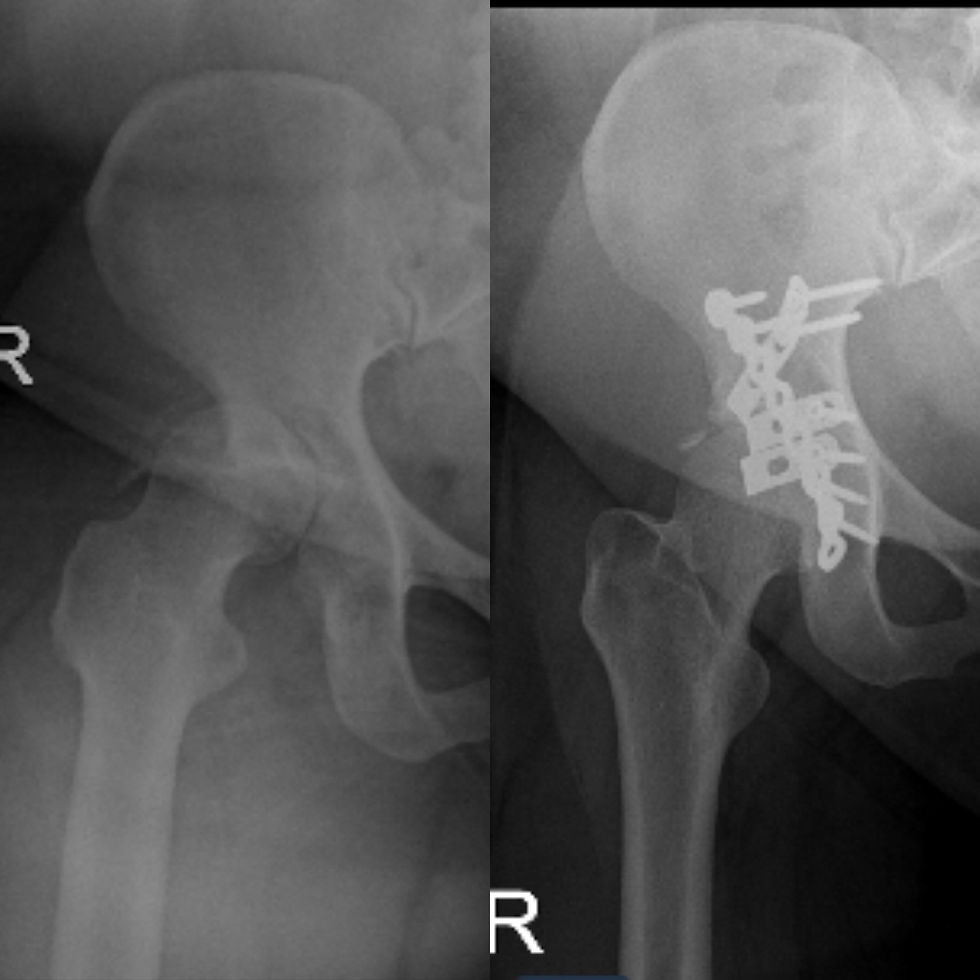

30 year old lady sustained motor vehicle accident. Right hip was fractured and dislocated. She underwent emergency surgery to relocate the dislocation and plate the fractured acetabulum. Repeated X-ray shows the fracture is healing well.

Wanita berusia 30 tahun mengalami kemalangan jalanraya. Tulang pinggul beliau terkehel dan patah. Beliau menjalani pembedahan untuk memperbaiki sendi pinggul dengan plet dan screw. X-ray menunjukkan kepatahan pada sendi pinggul sedang pulih kembali.